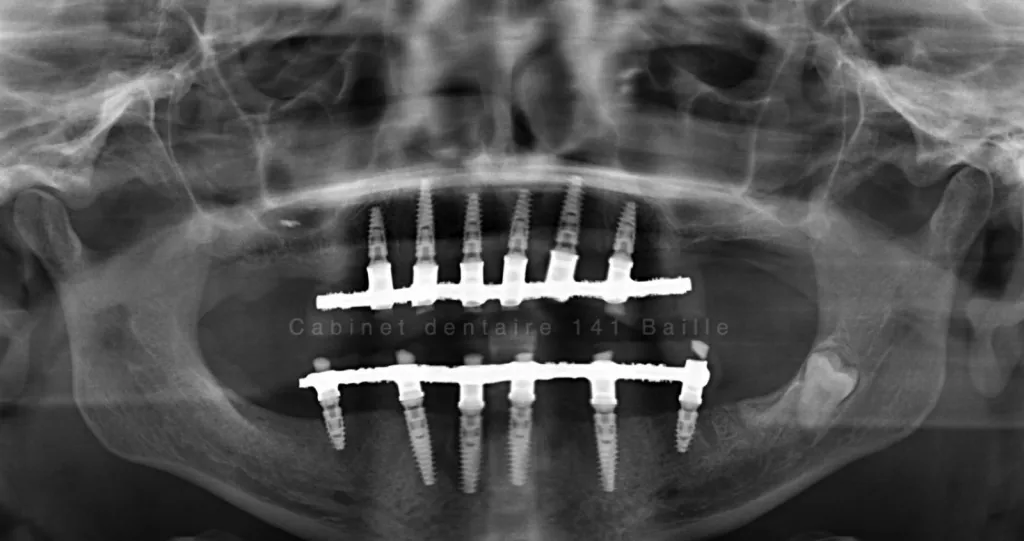

Bien que ces procédures allongent la durée totale du traitement implantaire, elles en sont souvent la clé de voûte. Elles transforment des cas complexes en succès prévisibles, permettant à des patients présentant une atrophie osseuse sévère de bénéficier quand même de la solution fixe et confortable des implants.

Si votre dentiste ou votre chirurgien a évoqué la nécessité d'une greffe osseuse ou d'un sinus lift, sachez qu'il s'agit de techniques maîtrisées et courantes, visant à maximiser les chances de succès de votre futur implant pour toute la vie.

Vous envisagez la pose d’un implant dentaire mais on vous a parlé de la nécessité d’une chirurgie pré-implantaire telle qu’une greffe osseuse ou un sinus lift ? Cette étape, bien que semblant allonger le processus, n’est pas une option, mais bien une condition sine qua non pour assurer le succès et la longévité de votre implant dans de nombreux cas. Poser un implant dans un os de qualité ou de volume insuffisant, c’est comme construire une maison sur des fondations fragiles. Découvrez pourquoi il est fortement indiqué, voire crucial, de recourir à ces techniques de chirurgie avancée pour garantir un résultat stable, esthétique et durable.

Un implant dentaire est une vis en titane qui joue le rôle de racine artificielle. Pour qu’il s’intègre de manière permanente et résiste aux forces de la mastication, il doit être entouré d’un os de qualité et en quantité suffisante. Ce processus d’intégration, appelé ostéointégration, est la clé de voûte de l’implantologie. Sans un environnement osseux adéquat, l’implant ne peut pas développer cette connexion intime avec l’os, ce qui mène inévitablement à son échec à moyen ou long terme.

En conclusion, la chirurgie pré-implantaire n’est pas une option, mais un passage obligé pour tout traitement implantaire qui vise l’excellence et la durabilité. C’est un investissement sage pour transformer un cas à risque en un succès prévisible, vous offrant ainsi la sérénité de bénéficier de vos nouveaux implants pour les décennies à venir.